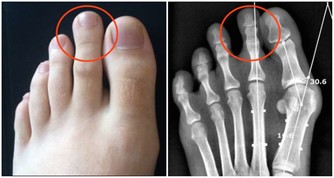

飲食不當會使某些食物攝入量超過機體的承受量;而營養不平衡也會對機體造成嚴重的危害;高糖、高脂肪飲食會導致心血管病;過量飲酒會損害肝臟;高蛋白質含量高的膳食可增加草酸鹽和尿酸的排泄引發結石